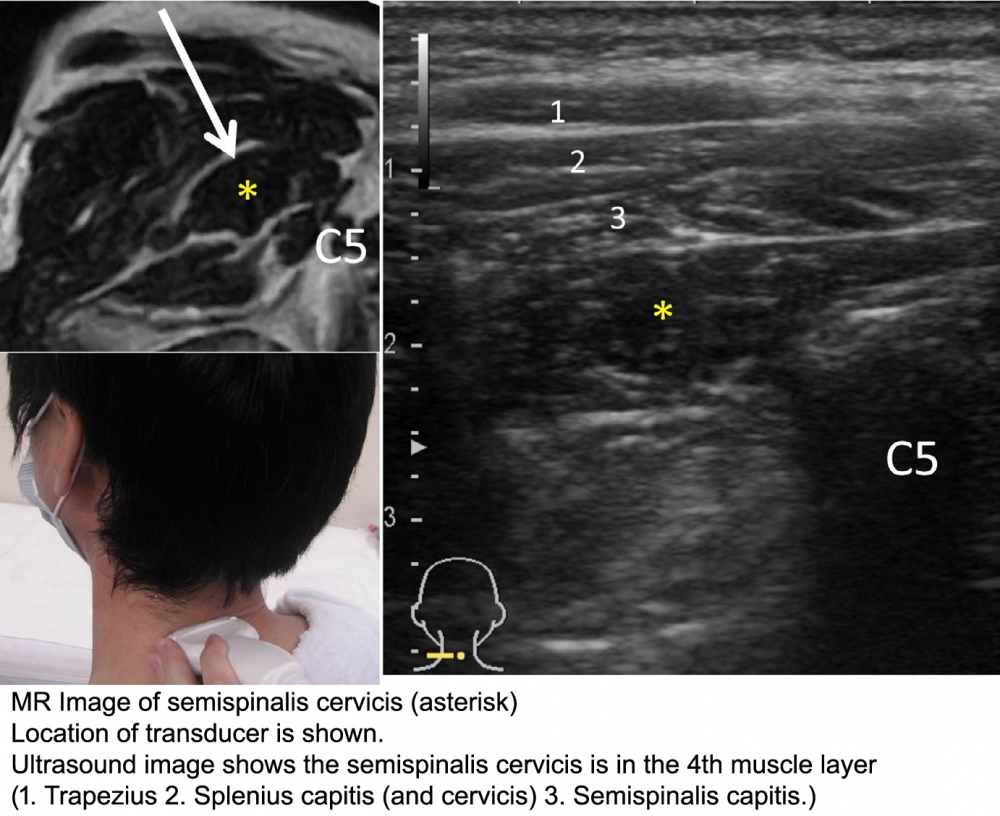

Technique: (from: Mezaki T. Ultrasoundâ€guided botulinum toxin therapy for deep muscles in cervical dystonia. Neurol Clin Neurosci 2020; 8: 3–10)

1. Place the linear transducer on the posterior aspect of the neck horizontally at the level of the posterior spinous process of the fifth cervical (C5) vertebra.

2. The muscle is found deep within the muscle layers of the neck: from superficial to deep, the layers consist of the trapezius, the splenius capitis (and cervicis), the semispinalis capitis, and then the semispinalis cervicis are identified. (Deep to this muscle, there is the multifidus muscle)